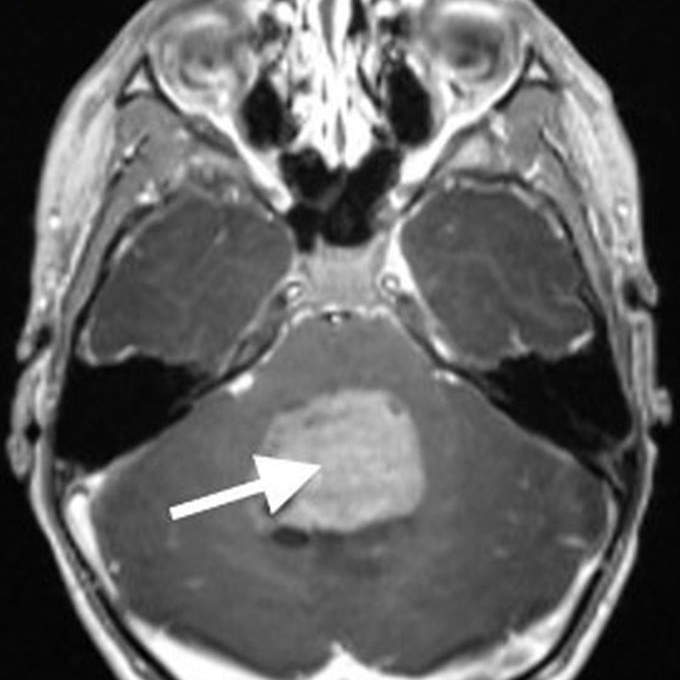

Imaging characteristics for the various subtypes of medulloblastoma are overall similar, reflecting that of densely packed, highly cellular tumors. Masses tend to be spherical in shape and displace adjacent structures, as opposed to the more pliable appearance of ependymomas. Increased density on CT and diffusion restriction on MRI are characteristic of medulloblastomas, reflective of their high cellularity. T2 signal intensity is variable, typically having areas of both increased and decreased T2 signal compared to cerebellar parenchyma. Small intralesional cysts are common, while intralesional hemorrhage and calcification are uncommon, though may occasionally be seen. Enhancement ranges from patchy to more robust solid enhancement [7, 8] (Fig. 1).

On MR imaging, DMGs present as a diffuse, ill-defined, T2 hyperintense, expansile masses centered within the pons. The degree of enhancement is variable, often absent at initial presentation and typically patchy when present (Fig. 3).